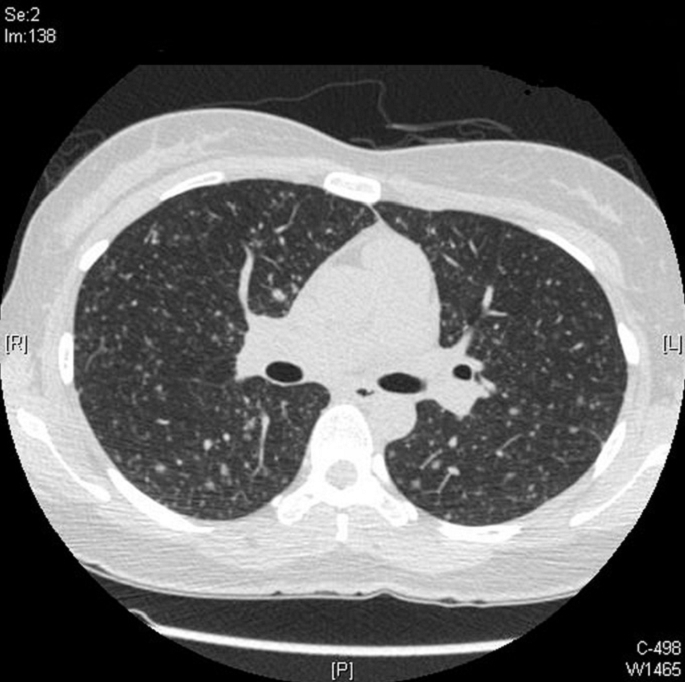

34¼¼ ¿©È¯

Ưº°ÇÑ Áõ»ó ¾øÀÌ CXR »ó ÀÌ»ó¼Ò°ßÀÌ ÀÖ´Ù°í Refer µÈ Case ÀÔ´Ï´Ù.

AFB Negative ÀÔ´Ï´Ù.

Chest PA, Chest CT »çÁøÀÔ´Ï´Ù.